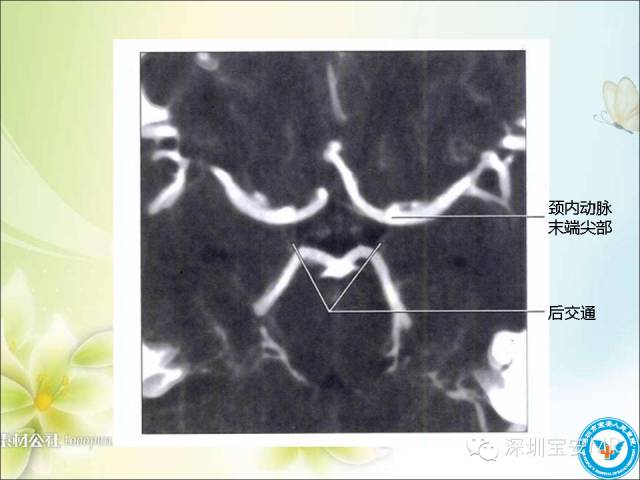

【PPT】颈内动脉颅内段影像解剖(附临床血管病例)